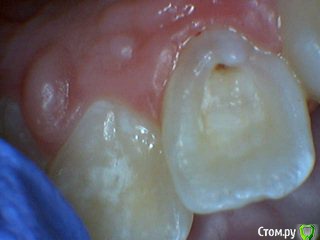

Давлетшин Опубликовано 13 июля, 2017 Поделиться Опубликовано 13 июля, 2017 Обидно понимаешь за детство, сообщений особо нет. подумать не над чем.два клинических случая. будут там пульпиты или нет? вот в чем вопрос. в одном случае пломба Витример в другом Эстелайт, без прокладок. Порядок фото несколько нарушен. Работаем над этим. Ссылка на комментарий

Давлетшин Опубликовано 13 июля, 2017 Автор Поделиться Опубликовано 13 июля, 2017 второй случай. один пациент 1 1 Ссылка на комментарий